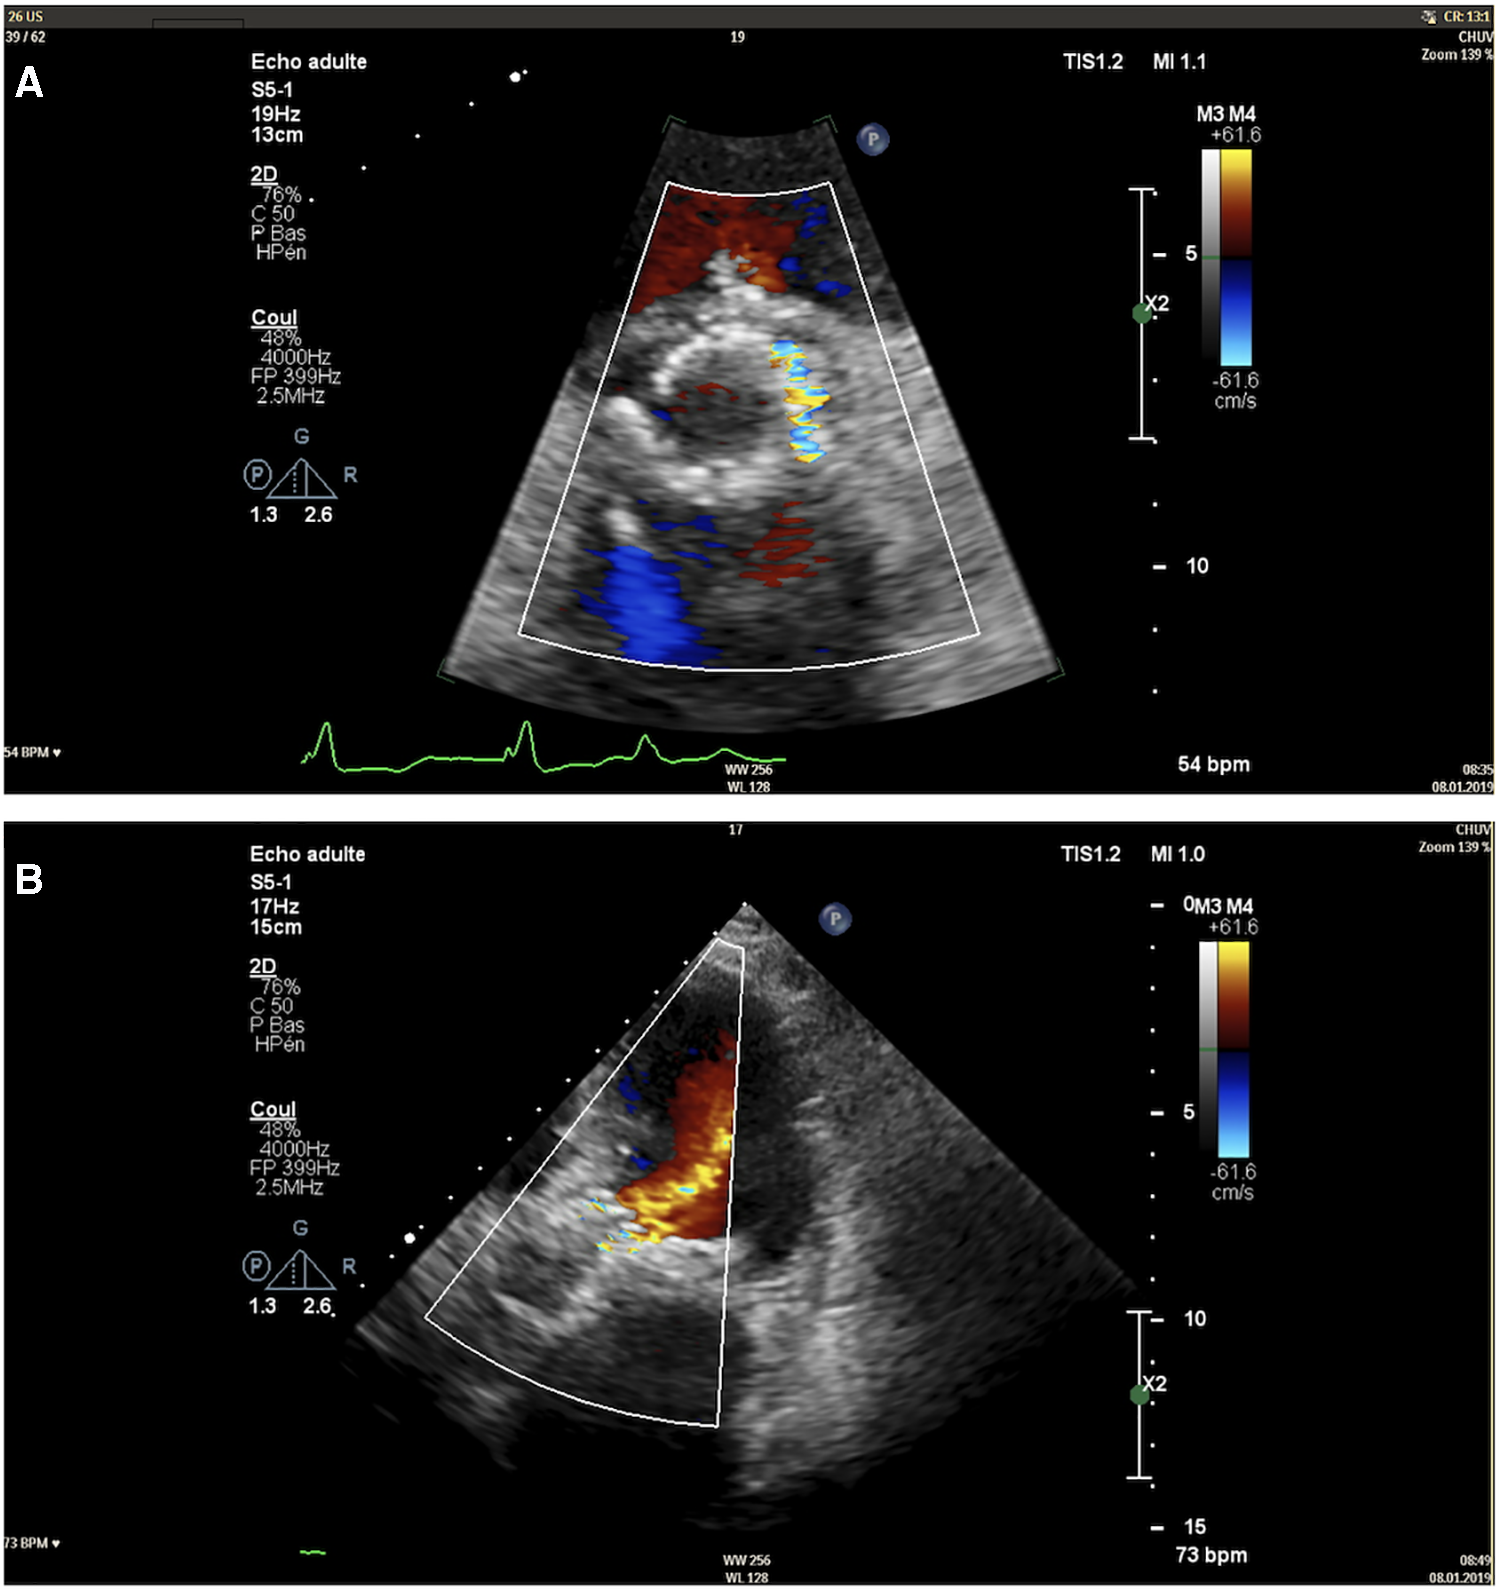

Five weeks after the valvular leak repair, the patient was readmitted for acute heart failure. At this time, echocardiography showed mixed aortic disease with aortic stenosis characterised by a surface of 1 cm2, a mean gradient of 23 mmHg, and a significant paravalvular aortic regurgitation involving 1/3 of the valve perimeter (Figure 3). The case was reconsidered by the Heart Team, and a surgical approach was proposed.

Figure 3

Transthoracic echocardiography image of the paravalvular leak in short-axis view (A) and apical five-chamber view (B).